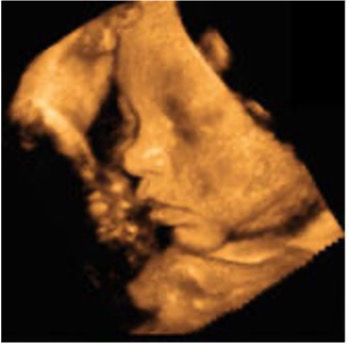

Gelişmekte olan bebeğin kafası üzerinde lanugo adı verilen ince ve ipeksi tüyler belirmeye başlar. Bu ilkel saçlar doğumda kaybolurlar. İkinci önemli haber ise bebeğinizin parmağını emmeye başlamasıdır. Ultrason altında bebeğin parmağını ağzına götürüp emdiğini doktorunuz size gösterecektir. Bu sadece anne karnındaki bir refleksidir. Her bebek anne karnında parmak emer diye bir kural da yoktur, ama ultrason incelemeleri esnasında sıkça rastladığımız bir durumdur.